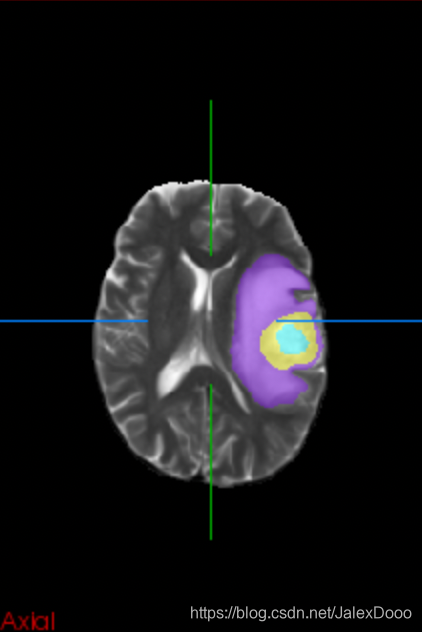

用在了大脑胶质瘤分割上,2D的处理方式,论文也是2D的处理形式,实在差劲;然后改成3D处理,还是差劲。

2D处理

看上去2D处理效果仿佛不错,但是